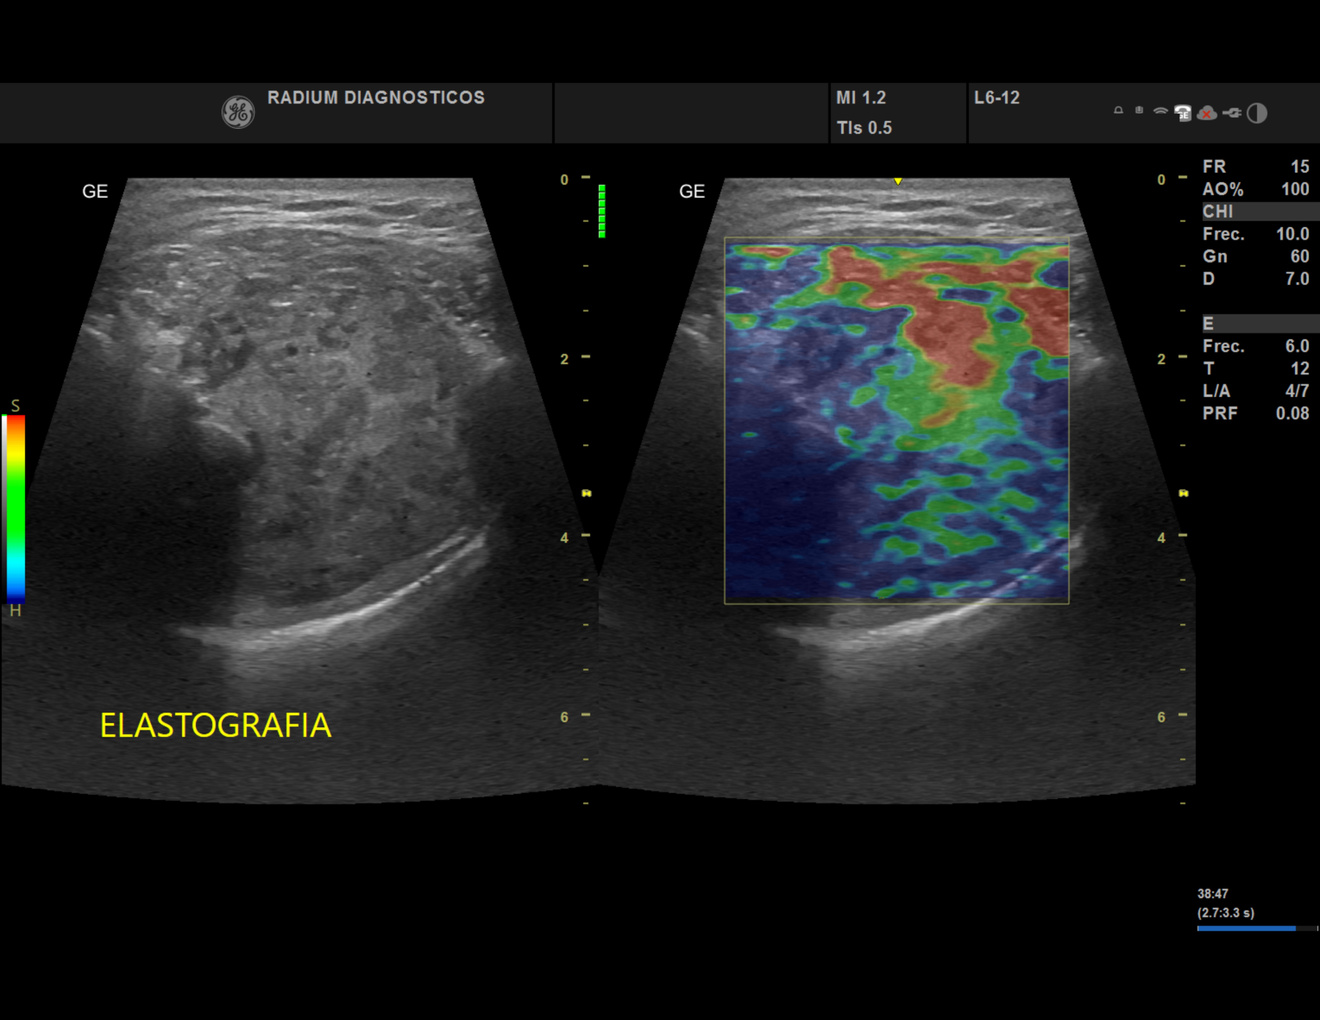

En centro de Imagen Radium ofrecemos estudios de Radiología e Imagen Médica de alta precisión a un precio justo, con equipos de última generación.

Imágenes de Alta Precisión.